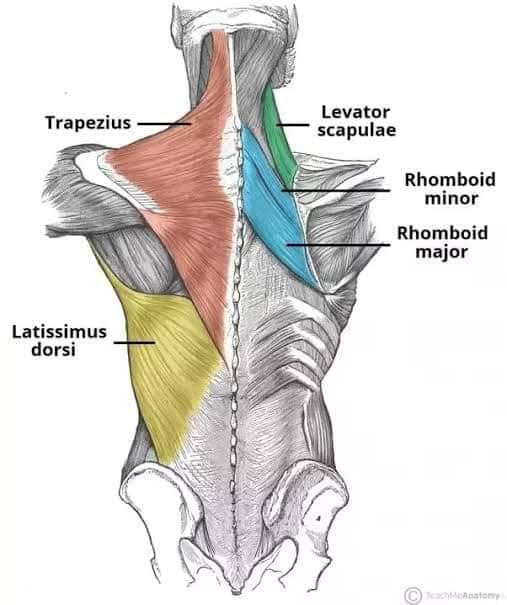

М'язи, що розширюють шию: М'язи, що розширюють шию: включають трапецієподібний м'яз, який бере участь у піднятті плечей і розширенні шиї.

Спинні м'язи

Спинні м'язи виконують функції підтримки хребта, а також дозволяють здійснювати рухи тулуба.

Поверхневі спинні м'язи

М'язи, що піднімають лопатку: Трапецієподібний м'яз: великий м'яз, що покриває верхню частину спини. Його функція - підтримка і рух лопаток, а також забезпечення стабільності хребта.

М'язи, що ведуть лопатку до хребта: Широкий м'яз спини: великий м'яз, що розташований в нижній частині спини. Він відповідає за рухи плечей і лопаток, а також за розширення верхньої частини тулуба.